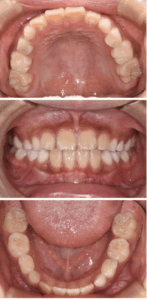

【 After 】

〈 年齢・性別 〉 5歳 女児

〈 主訴・相談内容 〉 反対の噛み合わせを改善したい

〈 診断名 〉 前歯部反対咬合

〈 装置 〉 プレオルソタイプ3

〈 抜歯部位 〉 非抜歯

〈 治療期間 〉 1年で改善、その後経過観察(3年間)

〈 治療費 〉 110,000円 (税別・精密検査代別)

〈 治療のリスク 〉 治療後の後戻り